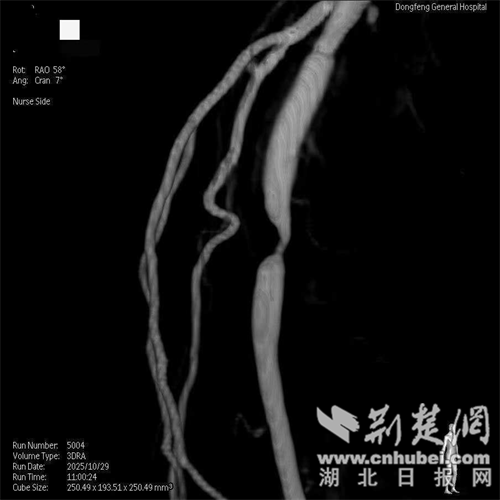

当他来到国药东风总医院就诊时,血管造影显示了一个残酷的事实——郝大爷的左侧腘动脉狭窄90%,双侧胫前动脉被切除。这就是他剧烈疼痛和行走困难的根源。

离开腘动脉前行斑块旋切术。通讯员供图

左腘动脉旋转斑块切除术后立即进行。通讯员供图